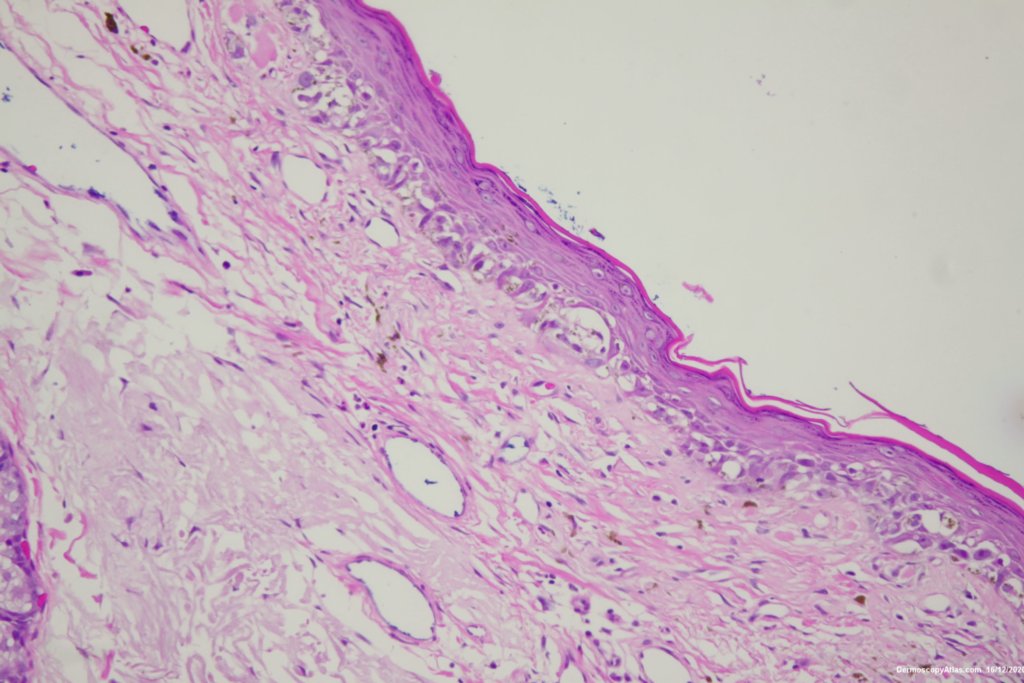

Diagnosis: Lentigo Maligna

Elderly male with no past history of melanoma developed these two lesions over a year or so. The lentigo maligna was easy to diagnose on the clinical and dermatoscopy but the nodule was more difficult. Was it an amelanotic melanoma, BCC or SCC were the initial thoughts. Histology showed a well differentiated sebaceous carcinoma. The two lesions were excised in the same specimen with 5 mm margins. Studies failed to show the mutation for the Muir Torre syndrome which can be seen with sebaceous carcinoma.